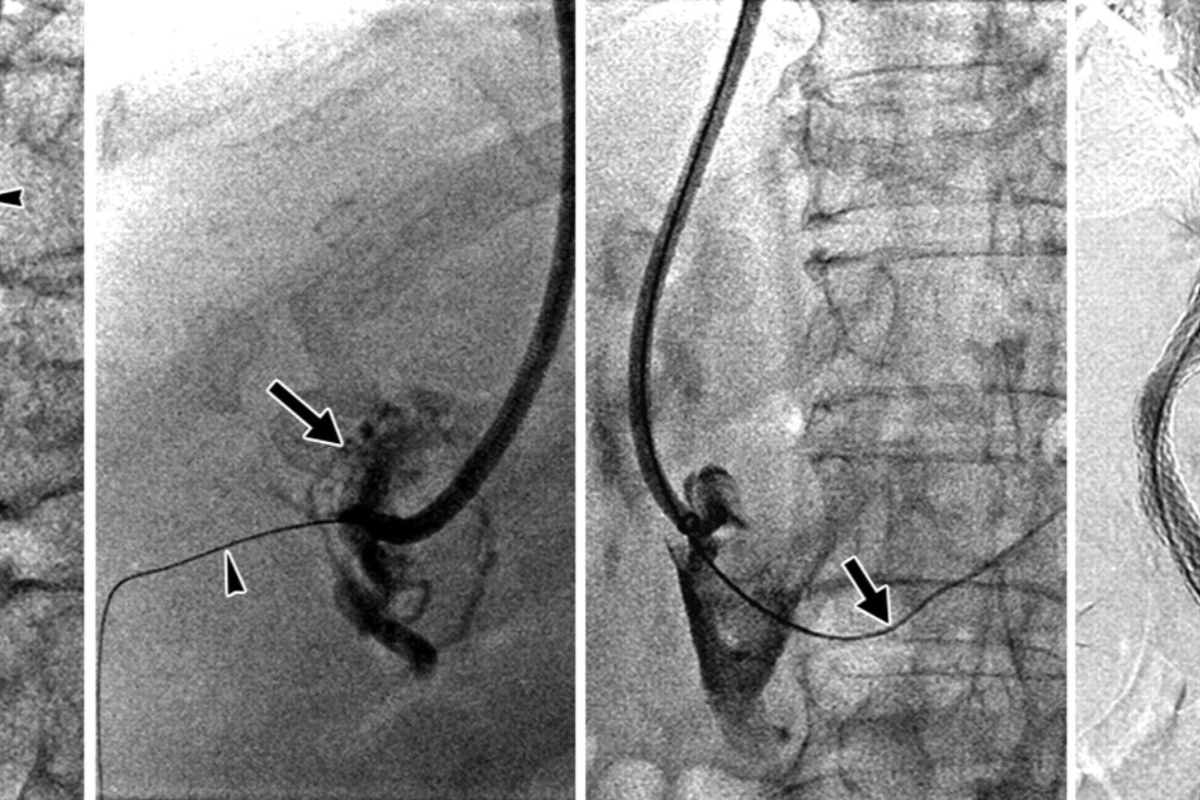

Peripheral Angioplasty procedure at Sarda Vascular Centre Dehradun

Interventional Radiology (IR) uses real-time imaging such as X-ray, ultrasound, CT, or MRI to guide tiny instruments through the body for treatment — without large surgical incisions.